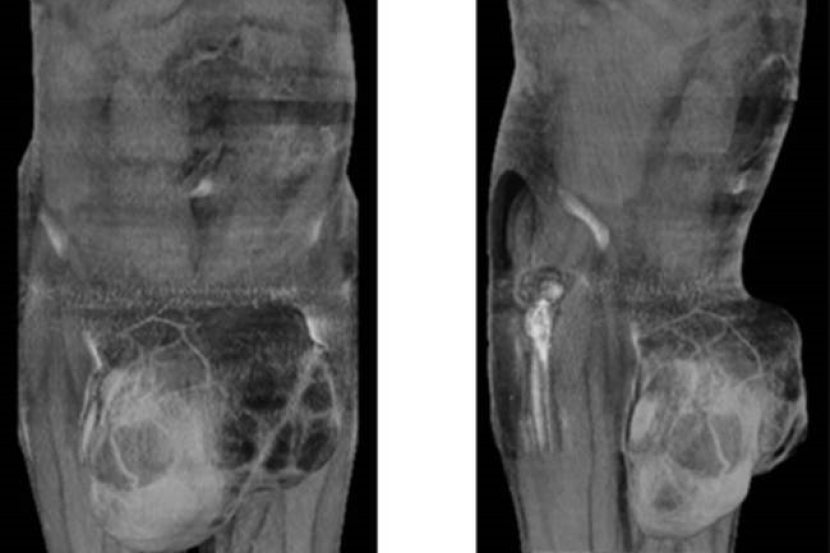

Selepas pemeriksaan doktor itu, Day yang menghidap penyakit kanser mendapat tahu ketumbuhan itu seberat empat kg.

Doktor mengesahkan bahawa ketumbuhan yang semakin membesar itu disebabkan kanser pada Krismas tahun lepas dan dia kemudian membuangnya pada Februari lalu.

Pakar bedah, Coonoor Chandrasekar melakukan pembedahan bagi membuang ketumbuhan pada buah zakar Day di Hospital Diraja Liverpool.